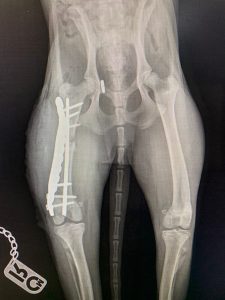

- Liječenje prijeloma kostiju, uključujući intraartikularne frakture

- Liječenje luksacije patele(Luxatio Patellae) Trohleoplastika i TTT(eng. Tibial Tuberosity Transposition)

- Liječenje rupture prednjeg križnog ligamenta koljena TPLO (eng. Tibial Plateau Leveling Osteotomy)